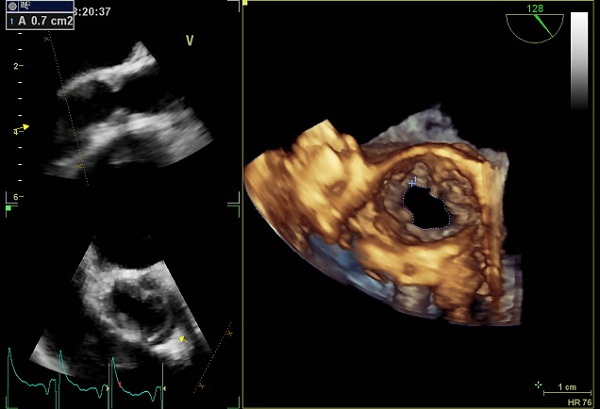

Tee 3d Image Philips Qlab Of The Aortic Valve Using The

Aortic Valve Anesthesia Key